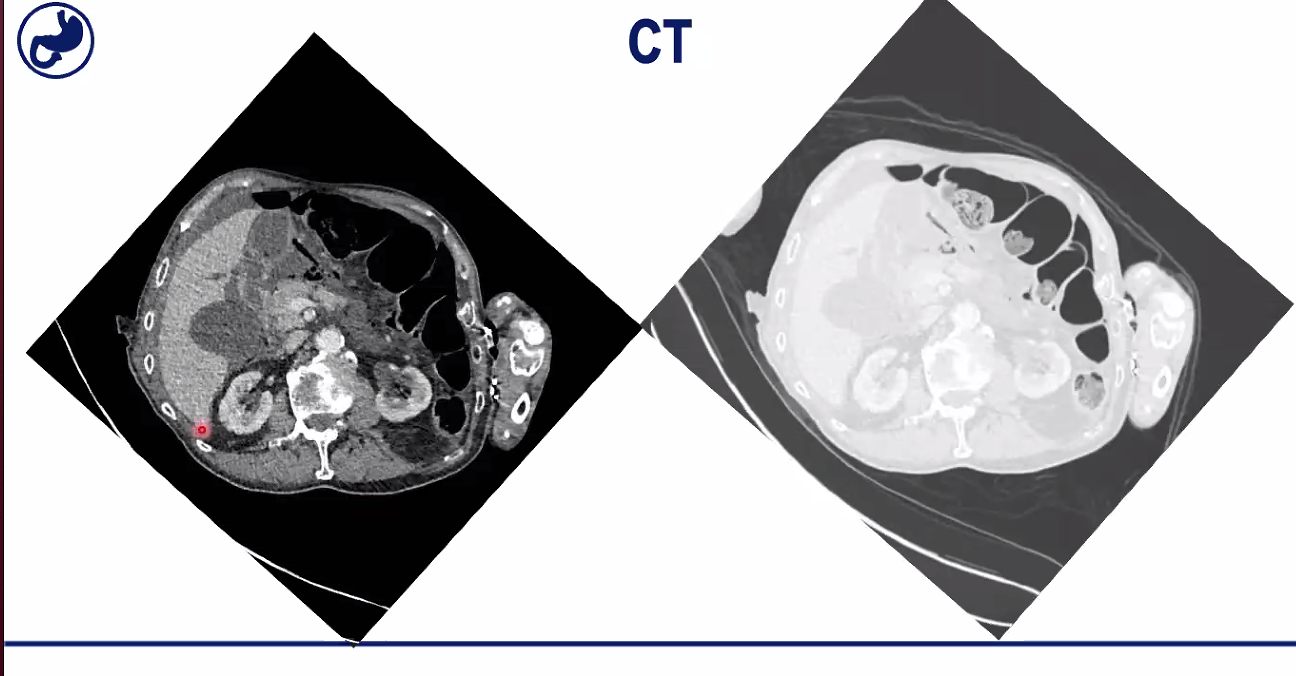

On right of image on left can see large bowel in black. Notice he has fluid around liver, which shouldnt be there. Can also see the pylorus, part of his stomach, coming down to his duodenum, and you’ll see there’s a defect here. So he’s had a pretty unusual duodenal perforation, and it’s been posterior.

The CT on the right has been adjusted so we can see where the air is.

Black is air inside large bowel and can see faeces inside it, and then can also see free air, that is outside the large bowel and that explains the Rigler’s sign. When got air on both sides, can see the walls very clearly.

Black is air. So can see slits of black which represent air in the abdomen near where the perforation is, so this gives you a clue where it is going on. So this is certainly a perforation and you can be pretty much 99% sure it’s coming from his duodenum.